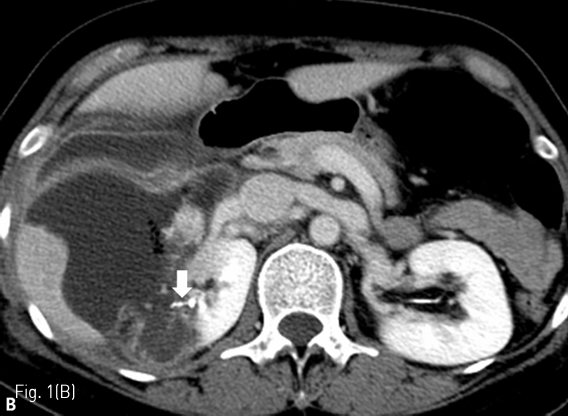

조영 증강 복부 전산화 단층촬영에서 우측 신장에 renal cell carcinoma로 생각되는 약 3cm 크기의 hypervascular tumor가 있다 (Fig. 1A) 우측 신장 부분 절제술을 시행 받고 5일째 복통을 호소하여 시행한 복부 전산화 단층촬영에서 수술 부위 주변으로 large urinoma with contrast leakage를 확인할 수 있다 (Fig. 1B).

Fig 1B

(B) On 5 days after the surgery, follow-up contrast enhanced CT shows large urinoma with contrast leakage (arrow) around the right partial nephrectomy site.